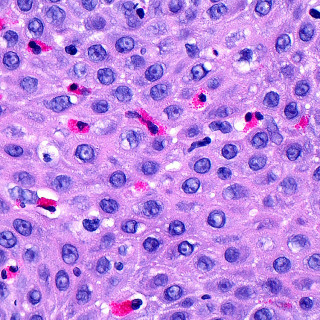

Indremedisin